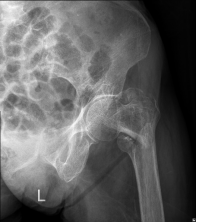

90岁的刘大爷,在洗澡时不小心滑倒至右侧“胯胯骨”痛,伴活动困难,由家属送至我院行X线片检查后诊断“股骨粗隆间粉碎性骨折”。大爷同时合并高血压、糖尿病、慢阻肺等多种基础疾病。入院后完善相关辅助检查,经过纠正贫血、电解质紊乱、调整血压血糖等积极处理,排除了绝对手术禁忌,在麻醉科、骨科团队的共同努力下成功为刘大爷实施了“股骨骨折闭合复位PFNA内固定术”,术中出血仅50ml,术后复查X片时骨折对位对线好,内固定可靠。在骨科医师及护理团队的尽心治疗及护理下,大爷恢复良好,术后5天可在助行器辅助下下地行走,术后2周正常出院。

“人生最后一次骨折”,即是老年髋部骨折,包括了股骨颈骨折、股骨粗隆间骨折。因其主要发生于老年人,而老年人身体机能较弱,且常合并高血压、糖尿病、冠心病等多种基础疾病,如未得到及时有效的治疗,短期内即可发生严重并发症(如深静脉血栓、肺部感染、褥疮等),其死亡率高达20%,且致残率高,42%的患者不能恢复伤前活动,35%不能独立行走,固被称为“人生最后一次骨折”。

多发于老年人,女性多于男性,通常由间接暴力(低暴力)或直接暴力(高暴力)引起,以间接暴力多见,如滑倒摔伤。典型表现包括髋部疼痛、肿胀、活动受限,局部皮下淤血瘀斑,患肢外旋短缩畸形。